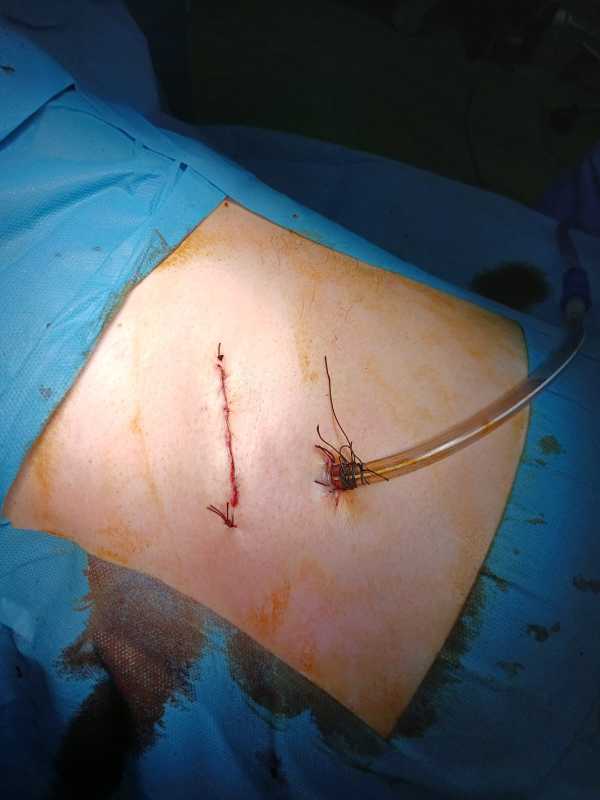

Operațiile sunt atât pe incizii clasice cât și minim invazive de tipul toracoscopiei, în funcție de patologia cazurilor.

'Trendul este către o chirurgie minim invazivă, care are numeroase avantaje: durata mai mică de spitalizare (implicit costuri mai mici), recuperarea pacientului este mai rapida, durerea postoperatorie este mai scăzută și mai bine tolerată, riscul infecțiilor intraspitalicești și al complicațiilor fiind mai mică, uneori aproape inexistente', spune chirurgul toracic.

Foto: dr. Alin Nicola